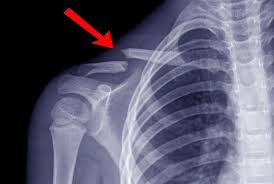

نهدف إلى تقديم خدمة طبية موثوقة وسريعة عبر تحليل الملفات الطبية والصور الشعاعية، ومنح المرضى رأيًا تخصصيًا واضحًا يساعدهم على اتخاذ القرار الصحيح في الوقت المناسب.

أقدّم من خلال هذا الموقع خدمة الاستشارات الطبية عن بُعد، بهدف مساعدة المريض على فهم حالته بشكل دقيق من خلال تحليل الصور والتقارير الطبية، وتقديم توجيهات طبية واضحة تساعده في اتخاذ القرار العلاجي المناسب.